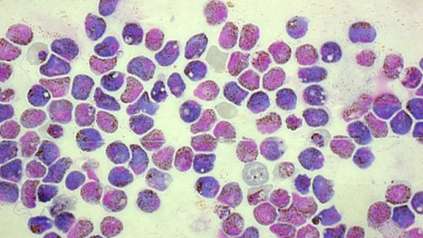

Science and Innovation

At the Wellcome Genome Campus we undertake both wet and dry lab science, basic research and the delivery of bioinformatics resources for the global scientific community.